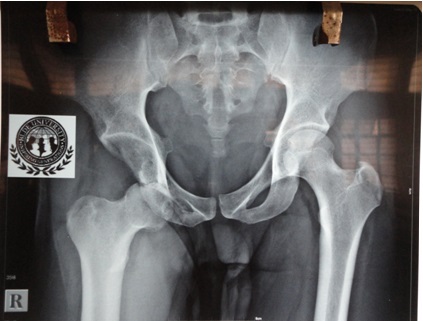

Radiological evaluation was done in the form of X-ray and MRI. X-ray of the pelvis with both hip joints (Figure 2) showed inferior dislocation of the femur with features suggestive of avascular necrosis of the head of the femur and flattening of the weight bearing dome of the acetabulum. MRI (Figure 3) showed a similar picture with conformation of antero-inferior dislocation of hip. The patient was advised total hip replacement and all pre-operative investigations were within normal limits.

Figure 3- MRI showing hip dislocation.